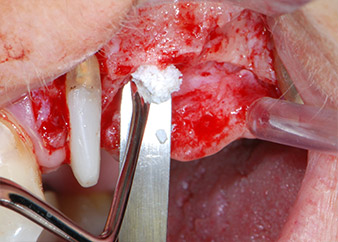

Prior to implant placement, and following verification of an intact Schneiderian membrane (Fig. 9), the internal sinus floor was augmented at both implant sites by means of xenogeneic bone substitute material (Bio-Oss, Geistlich Biomaterials) (Fig. 10).

integrity of the sinus membrane

Fig. 9: After implant bed preparation at site 26, the integrity of the sinus membrane was checked with a ball-ended CPITN periodontal probe.

CPITN-probe

Fig. 10: Introduction of xenogeneic bone substitute material into the implant osteotomy for internal sinus augmentation. The material was carefully condensed in an apical direction with the ball-ended CPITN probe (not shown).